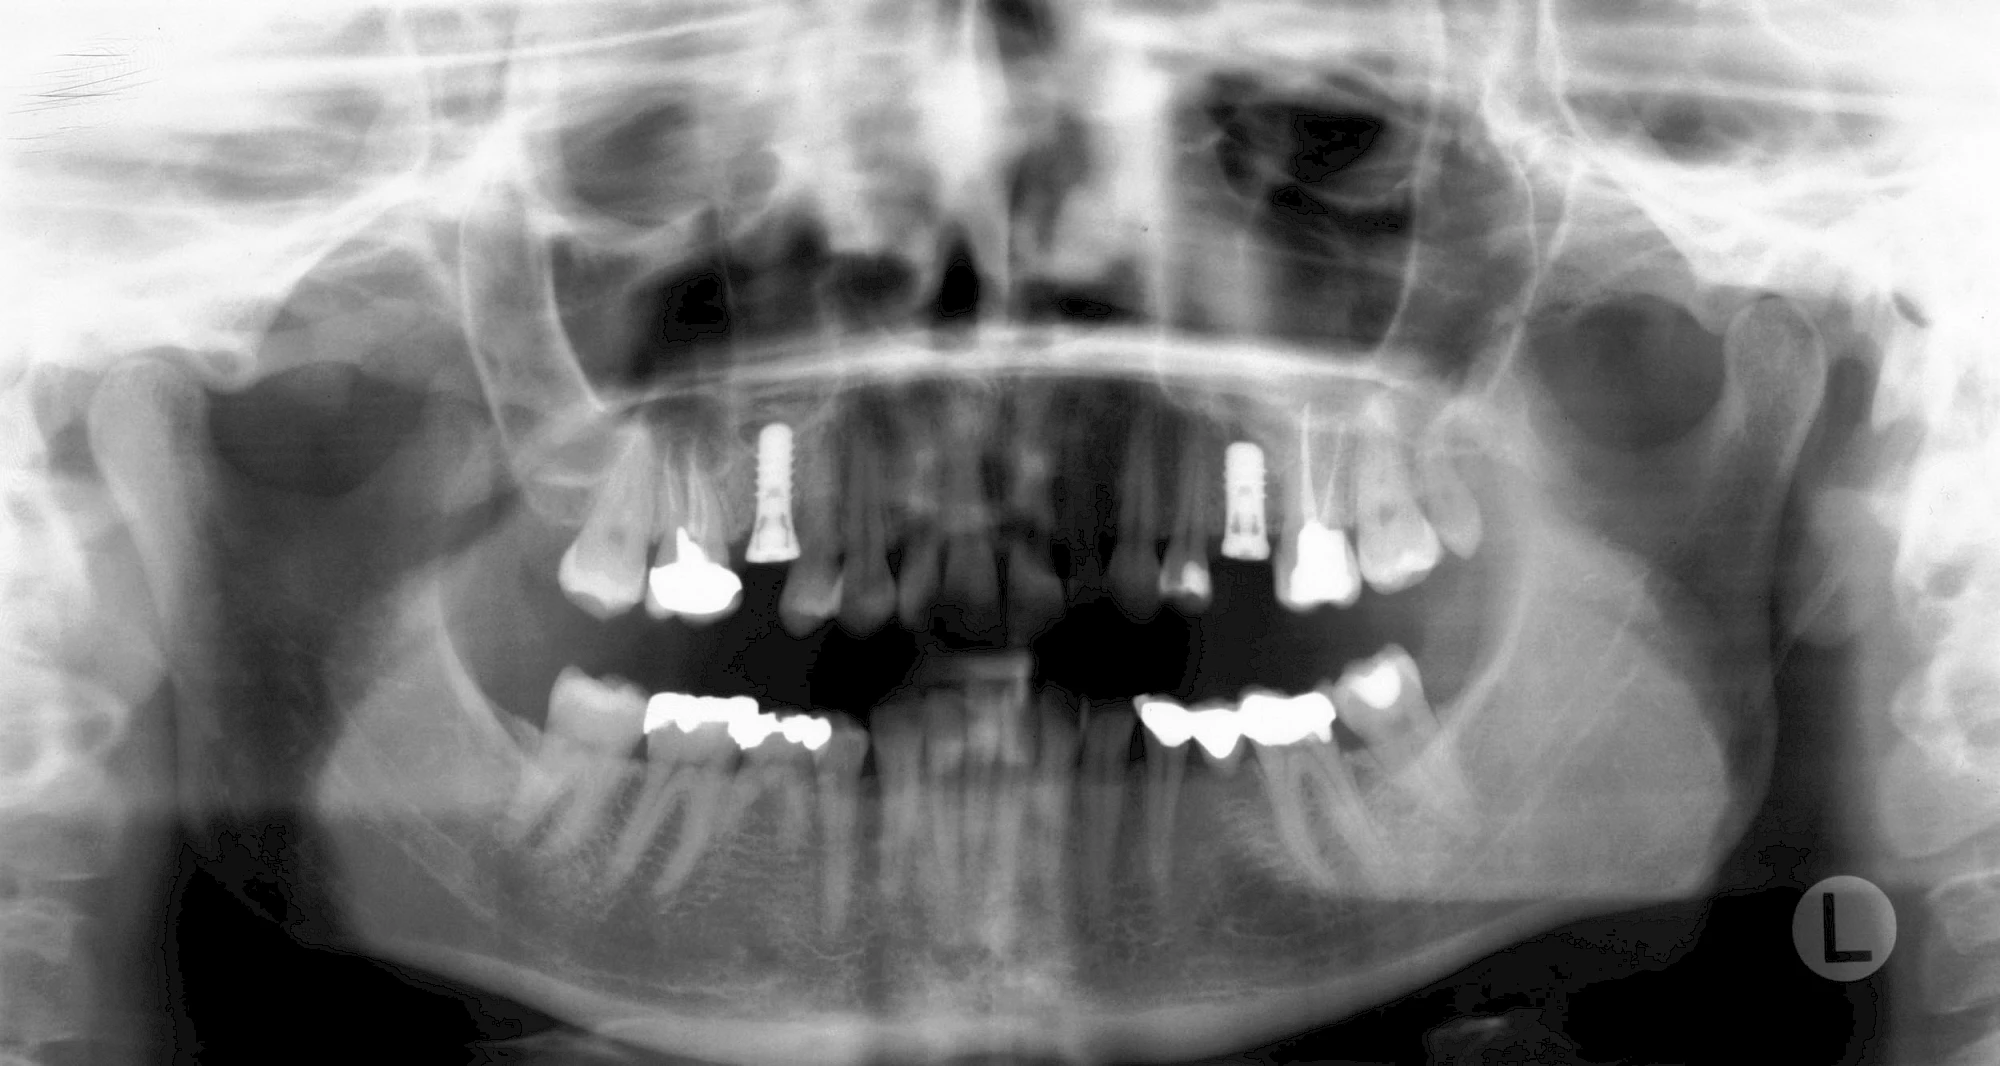

Fehlen einzelne Zähne und die Nachbarzähne sind unbeschadet oder gut zahnärztlich versorgt, werden immer häufiger Implantate gewählt, um die Lücken zu schließen. Auch bei größeren oder verteilten Lücken, wenn keine herausnehmbare Prothese gewünscht ist, werden Implantate für Kronen- bzw. Brückenversorgungen gesetzt. In Einzelfällen entscheiden sich sogar zahnlose Patienten für eine festsitzende Versorgung auf Implantaten.

Varianten zur Verankerung von festsitzendem Zahnersatz auf Implantaten

Implantatplanung

Damit Implantate an der richtigen Stelle im Kieferknochen platziert werden könen, gibt es heute vielfältige Möglichkeiten der Planung. In vielen Situationen kann die Erfahrung des Zahnarztes ausreichend sein.

Nicht selten ist jedoch auch eine technisch aufwändigere Vermessung im Vorfeld sinnvoll, z. B.:

- Wenn sich der Kieferknochen abgebaut hat

- Wenn der Nervverlauf im Unterkiefer beachtet werden muss

- Wenn die Ausdehung der Kieferhöhle im Oberkiefer beachtet werden muss

- Wenn wenige Restzähne keine gute Orientierung erlauben

In diesen Fällen kann die Planung mittels verschieden aufwendiger Röntgen-Techniken (Übersichtsaufnahme, DVT) ggf. unter Zuhilfenahme speziell angefertigter Planungsschablonen sinnvoll sein.